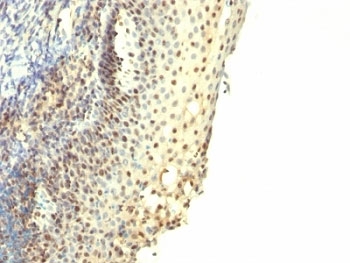

IHC: Formalin-fixed, paraffin-embedded human tonsil stained with IPO-38 antibody.

Recognizes a protein of 14-16kDa, which is a novel nuclear antigen of proliferating cells. IPO38 antigen is present in the nuclei of proliferating cells such as Hodgkin s disease and non-Hodgkin s lymphomas, different forms of leukemias, breast and colorectal carcinomas, and PHA-stimulated lymphocytes. It is not expressed in the cells of non-stimulated lymphocytes and granulocytes. IPO38 may be a useful marker of cell proliferation during monitoring of tumor progression.

Applications Immunohistochemistry (FFPE) : 0.5-1ug/ml for 30 min at RT